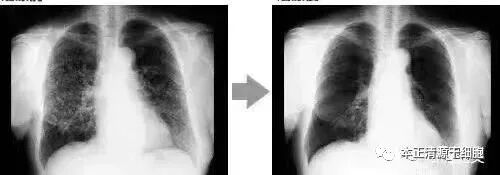

案例3:一名广泛期小细胞肺癌患者,在进行4个疗程化疗和4次高度活化NK细胞回输后,患者第一次进行干预后的CT复查,结果显示,肿瘤缩小到了原来的1/8。而且距发病第六年的CT复查中,仍旧没有发现任何异常及复发的迹象。